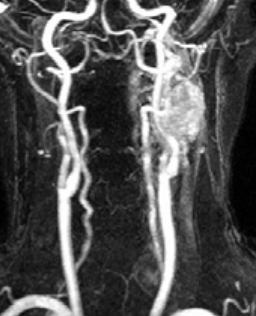

Paragangliome Carotidien

- Le plus fréquent (60%)

- Entre l’artère carotide interne et externe, les refoule